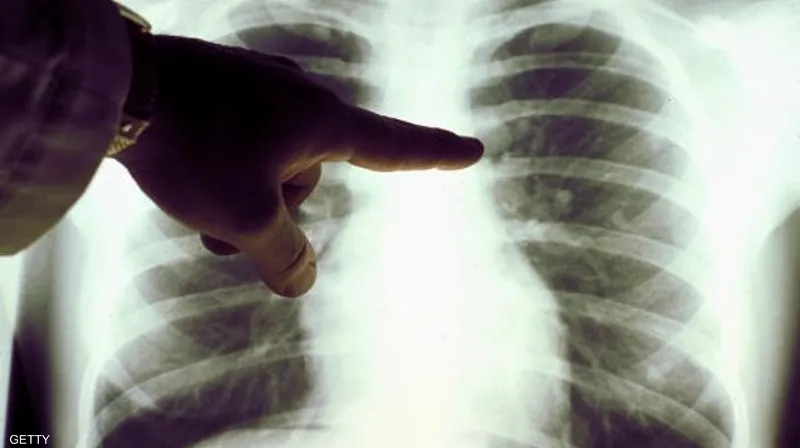

يحكي أحد المرضى عن تجربته مع جلطة الرئة التي أصابته فجأة أثناء ممارسته للرياضة، حيث شعر بألم حاد في الصدر وضيق في التنفس. بعد نقله إلى المستشفى، أُجريت له فحوصات طبية مكثفة، بما في ذلك التصوير بالأشعة المقطعية، والتي أكدت وجود جلطة في الرئة.

– التصوير المقطعي المحوسب: يستخدم في تصوير الأوعية الدموية بالرئتين للكشف عن أي انسدادات.

– تصوير الأشعة السينية للصدر: تُجرى هذه الطريقة بعد حقن مادة ملوّنة لتسهيل رؤية الأوعية الدموية وتقييم حالتها.